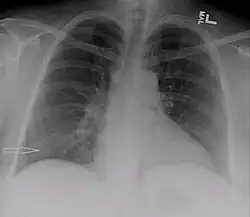

| Derrame pleural no lado direito causado por urinotórax | |